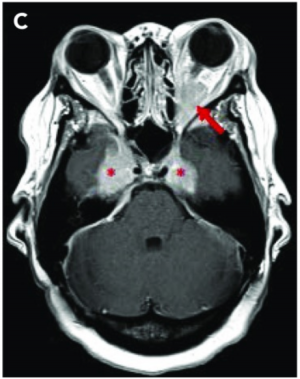

Imaging with CT, MRI, and ultrasonography may be helpful to characterize the lesion. [9] [10] Osteolytic bone lesions are present in less than 10% of cases. [5] Soft tissue lesions are enhancing on CT and MRI. PET imaging demonstrates a hypermetabolic state.